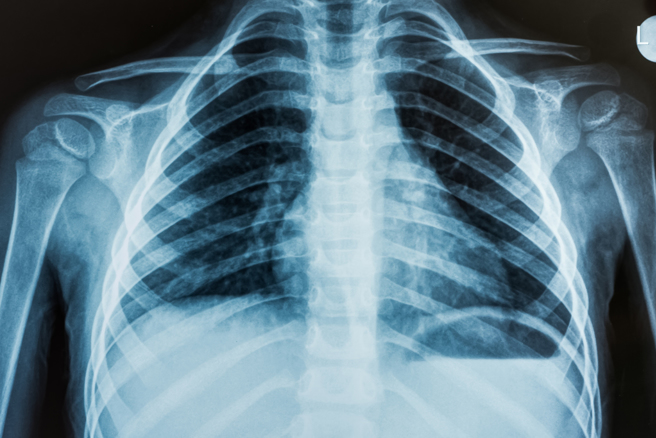

他说明,血管粥状硬化的过程会有异常发炎和增厚,造成细胞死亡和组织间质堆积,导致一些矿物质沉积在血管壁,即「钙化现象」。因为X光检查的特性,很容易显示胸部或是腹部的X光片中主动脉的管壁上有白色、晶亮的钙化斑块。

刘中平表示,最新的研究显示,X光片上有主动脉钙化的人会增加2成以上的心臟病及死亡风险,这是因为机转类似,主动脉发生钙化,心臟的冠状动脉也易有钙化,日后会发生心臟缺氧和心绞痛。此外,主动脉的钙化斑块若剥落,有可能流入颈动脉、阻塞脑循环,造成脑中风。